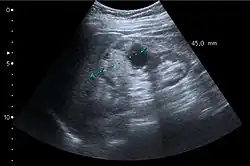

Unspecific cortical lesion on CT scan is confirmed cystic and benign with contrast-enhanced renal ultrasonography.

Renal cell carcinoma with both cystic and solid components located in the cortex. Measurement of tumor on the US image is illustrated by ‘+’ and a dashed line.[3]